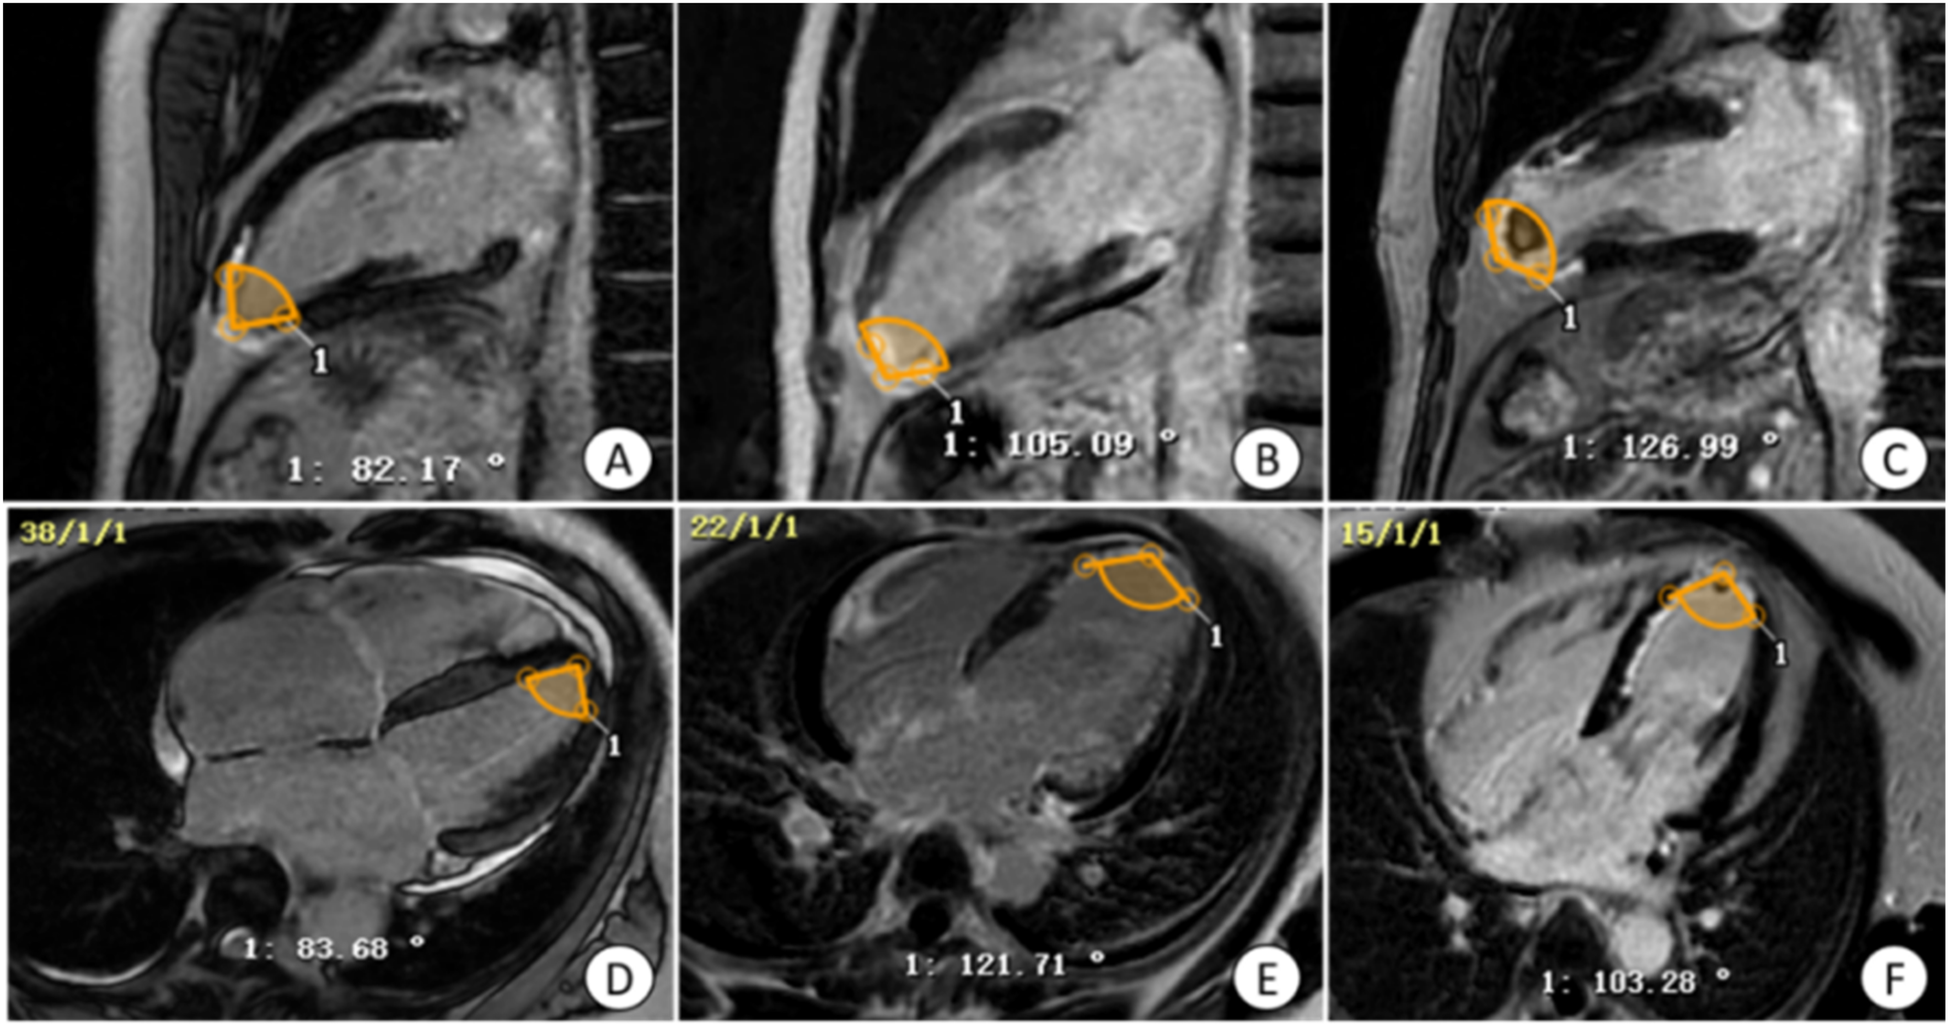

Figure 2

Manual measurement of apical angle on LGE image. (A,D) Patients with non-ventricular wall aneurysms, the apical angle is 82.93°; (B,E) patients with early ventricular wall aneurysms, the apical angle is 113.40°; (C,F) patients with early ventricular wall aneurysms with appendage thrombosis, the apical angle is 115.12°. The yellow markers show the apical angle. LGE, delayed gadolinium enhancement.

2.2.2.3 Apical angle analysis

To measure the apical angle, the four-chambered heart and left ventricular outflow tract (LVOT) levels of the LGE sequence were used. Taking the LVOT apical level as the starting point, a line segment with a length of about 1–2 cm was drawn on both sides of the endocardium respectively, and the apical angle was calculated by measuring the angle between these two line segments. The apical angle was measured and averaged at the four-chamber heart and LVOT levels, respectively, to derive the desired apical angle data (Figure 2).

For patients with morphologically atypical early ventricular wall aneurysms, in addition to observing ventricular wall motion abnormalities and measuring ventricular wall thickness, the present study found that measuring the size of the apical angle could improve the sensitivity of the diagnosis of early ventricular wall aneurysms, and that the apical angle of the patients in the ventricular wall aneurysm group was mostly obtuse, whereas the angle of the patients in the non-ventricular wall aneurysm group was mostly acute, which was statistically significant in the multifactorial logistic analysis. It was also found that patients with acute anterior wall myocardial infarction and early combination of ventricular wall aneurysms had the most susceptible apical involvement, and in the present study the ventricular wall aneurysms were located in the apical region, which may be due to the uncoordinated motion of the ventricular layer caused by the increasing apical angle of the ventricular wall expanding outward. According to the results of the ROC curve analysis, the critical value for the diagnosis of early ventricular wall aneurysm formation using the apical angle was 90°, and the risk of early ventricular wall aneurysm development increased by 23.8% with each 1° increase in the apical angle, a model that demonstrated a high sensitivity (94.4%) and a relatively low specificity (72.2%). These metrics emphasize the usefulness of apical angle as a tool for diagnosing early ventricular wall aneurysm formation, but also suggest that its specificity is relatively low and requires further study and validation.